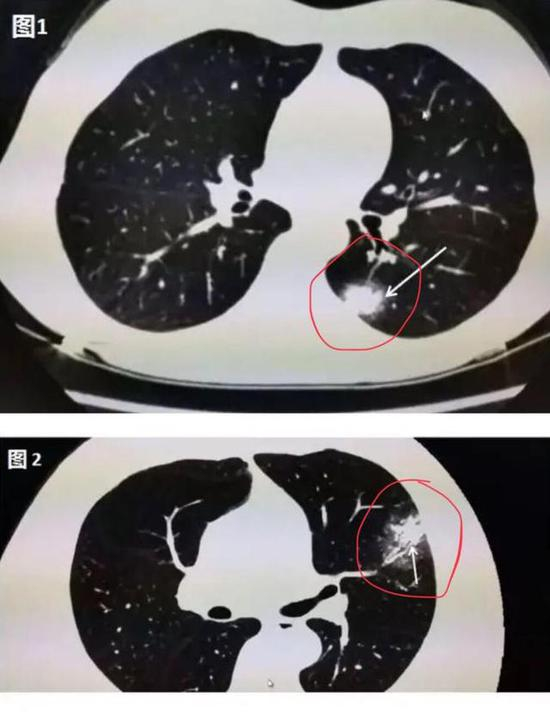

其实,在疾病早期,肺部CT上可能并不会首先出现磨玻璃影。华中科技大学同济医学院附属同济医院放射科管汉雄教授发文称,患者一旦出现咳嗽、持续发热、不明原因乏力时,CT常常会有阳性发现。肺部CT上可能出现一白色不规则的小斑片(如图1箭头所指区域),即“实变结节影”,或者是中央实变、周围磨玻璃(如图2箭头所指区域),也就是中央区域是一白色不规则的小斑片,周围则像云雾状磨砂玻璃一样。随着病毒的持续“攻击”,病情发展,感染加重,白色的实变结节区域开始吸收,如同一颗糖融化了一样,慢慢变为磨玻璃影。

▲图1:肺部CT上出现一白色的小斑片; ▲图2:中央区域是一白色的小斑片,周围则像云雾状磨砂玻璃一样(图片来自网络)